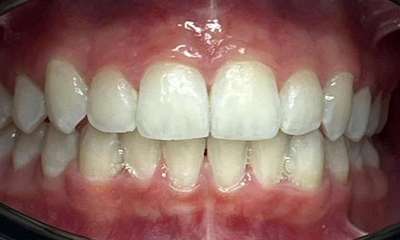

What a smile! It’s so nice to see Invisalign in progress and the confidence it brings, even in the process. In this case it took nine months of Invisalign clear aligners for Dr Gourlay to correct this patient’s crowding. The patient and family are thrilled with the result.